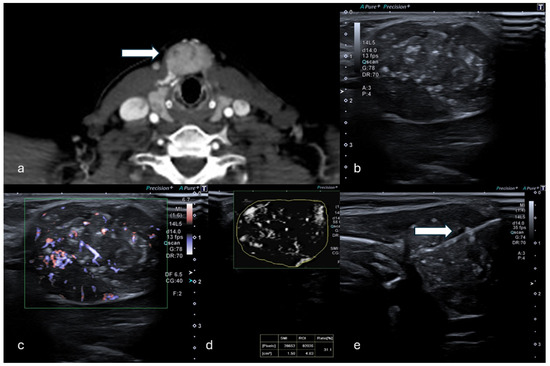

Figure 1.

(a) Coronal CT reconstruction in venous phase shows a hypodense 16 mm solid nodule of the spleen (white arrow). (b) B-mode US showed a dishomogeneous hypoechoic focal lesion with halo sign. (c) At mSMI, peripheral and central globular vessels were appreciable, VI measuring 40.5%. (d) Percutaneous biopsy using an 18G needle (white arrow). (Histological examination reported a lung cancer metastasis.).